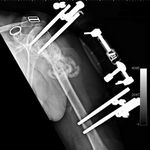

She was advised of the need to do some sort of stabilization which is necessary since the use of low-dose ultrasound has not helped in the healing process. She was unwilling to have any further operative intervention and sought further options. Eventually, she agreed to a fourth procedure of intra-medullary nail stabilization of the fracture and had this carried out in April 2011. An intramedullary nail was inserted in an antegrade manner and she has since gone on to heal the fracture site completely and has regained most of the function of the upper limb with no pain.

This case illustrates the possible complications that can occur with any surgery but also our commitment to our patients by sticking with them and making sure that a positive outcome is had despite the many challenges that may arise.